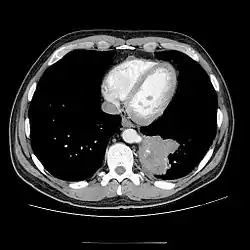

CT

- CT scans have 90% accuracy in the diagnosis of pulmonary sequestration.

- The most common appearance is a solid mass that may be homogeneous or heterogeneous, sometimes with cystic changes.

- Less frequent findings include a large cavitary lesion with an air-fluid level, a collection of many small cystic lesions containing air or fluid, or a well-defined cystic mass.

- Emphysematous changes at the margin of the lesion are characteristic and may not be visible on the chest radiograph.